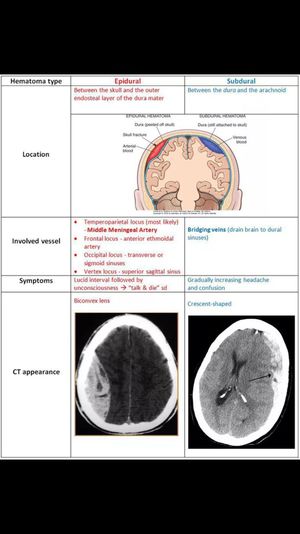

Brain

Xray

Ct

Scan